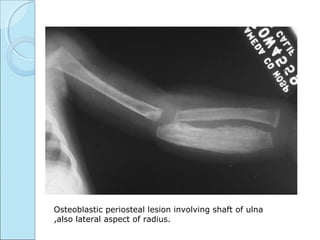

CAFFEY’S DISEASECAFFEY’S DISEASE

 INFANTILE CORTICAL HYPEROSTOSIS.

RADIOGRAPHIC FEATURESRADIOGRAPHIC FEATURES

 Marked periosteal proliferation.

 Cortical thickening.

 Soft tissue swelling.

Osteoblastic periosteal lesion involving shaft of ulna

,also lateral aspect of radius.

Deformity, periosteal reaction. Soft tissue

swelling.